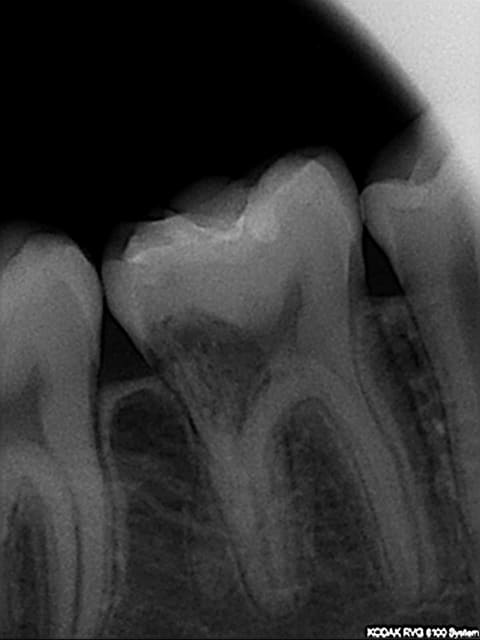

Patient de 14 ans

découverte sur pano d'une image radioclaire au niveau caméral de 46.

Pour moi il s'agit plutôt d'une résorption externe.

La proximite pulpaire de la resorption fait que sans pratiquement aucun doute il y a une communcation pulapire. Le traitement endodontique sera inevitable.

Deuxieme chose, l'application d'acide trichloracetique dans ce cas ne sera pas facile mais nécessaire. Pour accéder a la lesion, il te faudra lever un lambeau, dans un tissu extremement hemorragique car inflammatoire. Le niveau osseux se situe en dessous du niveau de la résorption. Une osteoplastie sera donc necessaire.

le probleme a gérer sera donc définitivement plus complexe sur le plan parodontal que sur le plan endodontique.